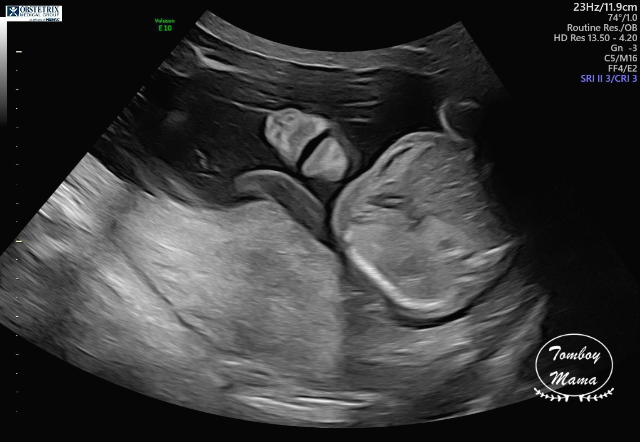

여기서 잠깐 보고 가는 튼튼이 20주차 (정확히는 19주 6일차) 초음파 사진들!

(1) 태아도 건강하고, 크기도 딱 좋고 (하루만큼 더 커서 20주 0일 크기), 다 좋단다.

(2) 단, 태아의 뇌에 낭종(choroid plexus cyst)이 있는데, 주로 다운증후군과 연관이 있는 증상이라고 했다. 자연스럽게 사라질 수도 있는 거고, 아이큐에 영향을 준다던가 하는 그런 문제가 아니기 때문에, 이게 발견되었다고 나중에 따로 추적하지는 않는다고 했다. 다만 다운증후군 가능성이 염려되면 (바늘로 찔러서 하는) 양수 검사를 할 수 있는데, 솔직히 지금 나에게는 추천하지 않는다며 3가지 이유를 얘기했다.

a. 정밀 초음파 검사 결과 이 외의 다른 증상이 보이지 않고, 모두 정상으로 보임.

b. 아기의 크기가 정상적으로 잘 자라고 있음.

c. NIPT 및 NT 테스트 결과가 이미 음성이었음.